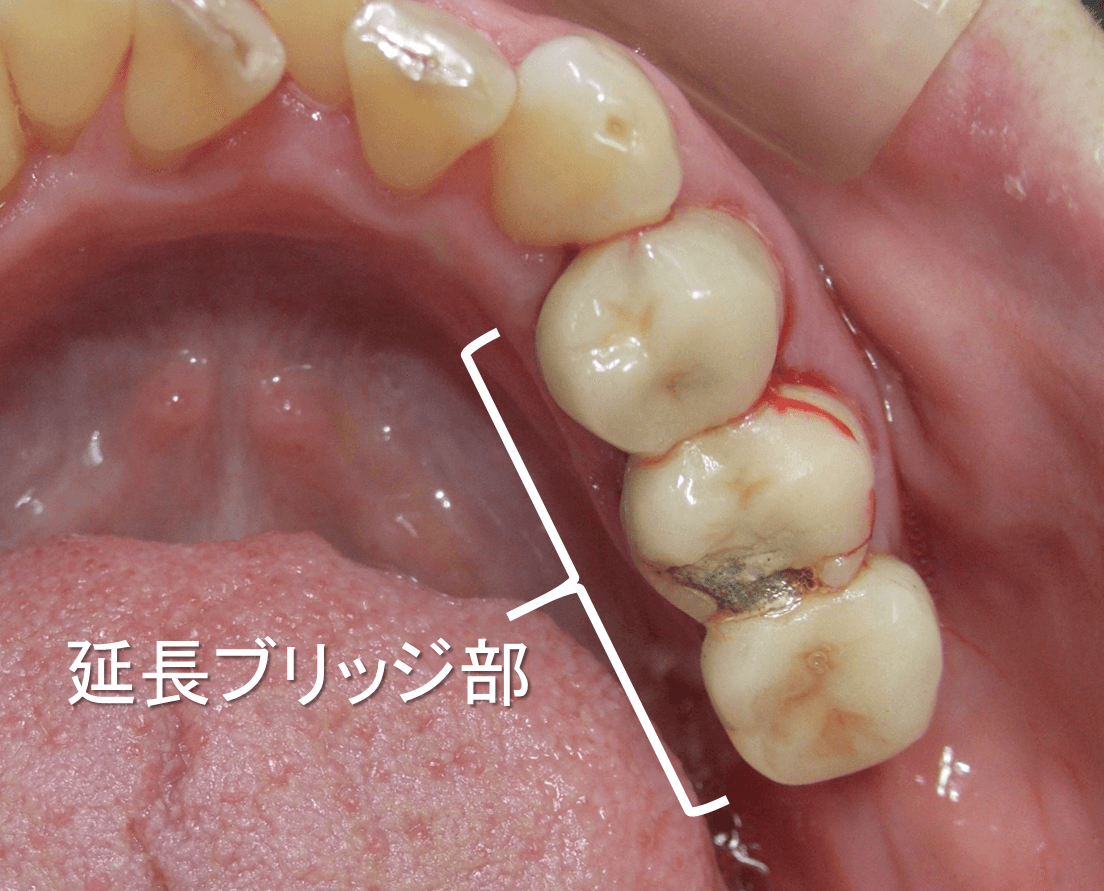

インプラント治療で回復したケース

こんにちは。 南館歯科クリニックの院長の木村です。 左下臼歯部(奥歯)の欠損部をインプラント治療で回復した50代の女性のケースをご紹介します。 治療前の状態。 左下奥歯には、延長ブリッジ…